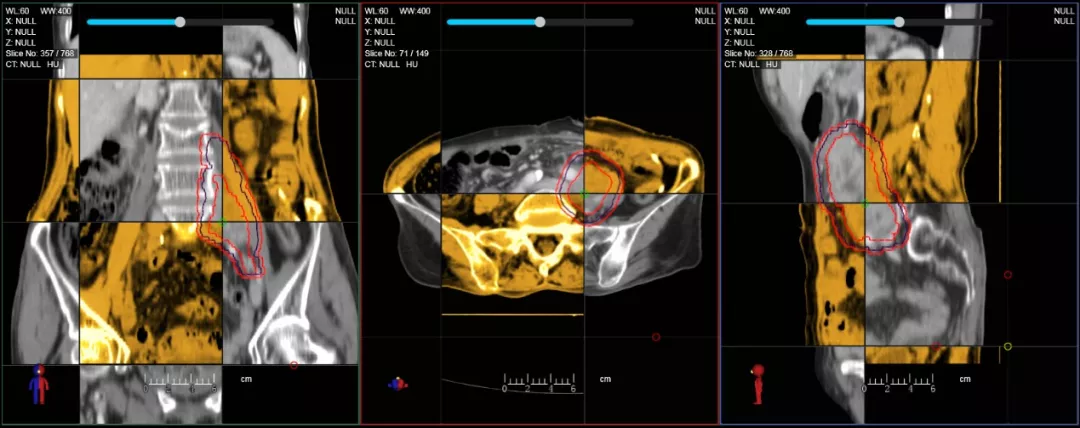

個體化自適應(yīng)放療

一體化CT-linac讓自適應(yīng)放療ART概念變?yōu)楝F(xiàn)實?;颊呷煶虪顟B(tài)監(jiān)控,適時在線調(diào)整治療計劃,精準控制治療劑量,為患者動態(tài)定制個體化治療方案。uAI賦能智能勾畫和自動計劃,秒級勾勒靶區(qū)和危及器官,大幅縮短自適應(yīng)放療時間。